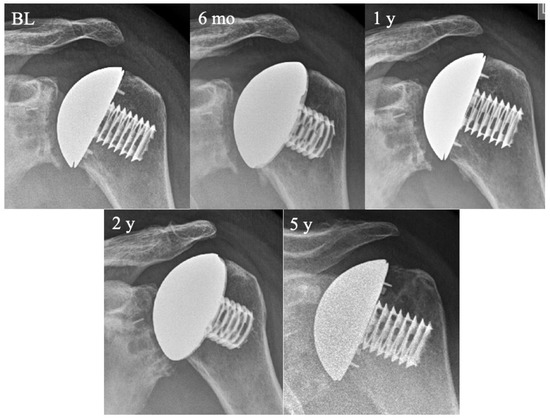

3.4. Association between Radiographic Parameters and CS and SSV across Time Points

| Radiographic Parameter | Six Months | One Year | Two Years | Five Years | p-Value (Two Years vs. Six Months) | p-Value (Five Years vs. Six Months) |

|---|---|---|---|---|---|---|

| Acromiohumeral distance (mm) | 12.7 (0.3) | 12.5 (0.3) | 12.1 (0.3) | 10.4 (0.4) | 0.17 | <0.001 |

| Lateral humeral offset (mm) | 52 (0.3) | 51.9 (0.3) | 51.5 (0.3) | 50.5 (0.4) | 0.02 | <0.001 |

| Joint gap width (mm) | 2.9 (0.1) | 2.8 (0.1) | 2.6 (0.1) | 1.4 (0.2) | 0.17 | <0.001 |

| Franklin radiolucency grade | 2.2 (0.1) | 2.7 (0.1) | 3.1 (0.1) | 3.8 (0.1) | <0.001 | <0.001 |